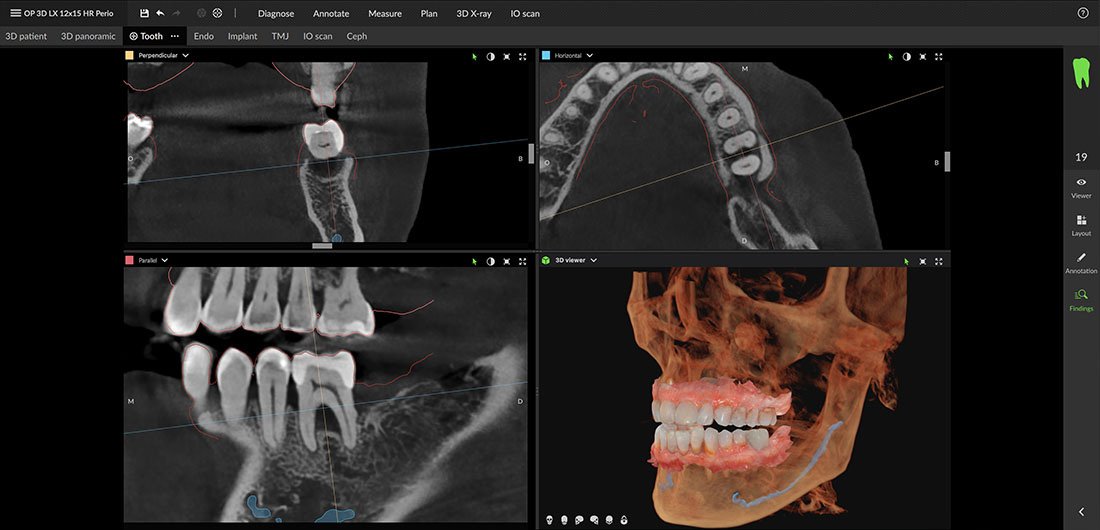

Endodontia

A DEXIS OP 3D LX dedikált endofelbontásával és precíz szkennelési pozicionálásával úgy lett optimalizálva, hogy a legkisebb részleteket is megjelenítse, melyek mind fontosak lehetnek az endodontiai diagnózis és kezelés szempontjából.

Parodontológia

Az OP 3D LX lehetővé teszi a csontszerkezet valamint a sinus és az ideg elhelyezkedésének teljes körű vizsgálatát, biztosítva ezzel a csontvesztés kezelésére szolgáló lehetőségek pontos meghatározását.